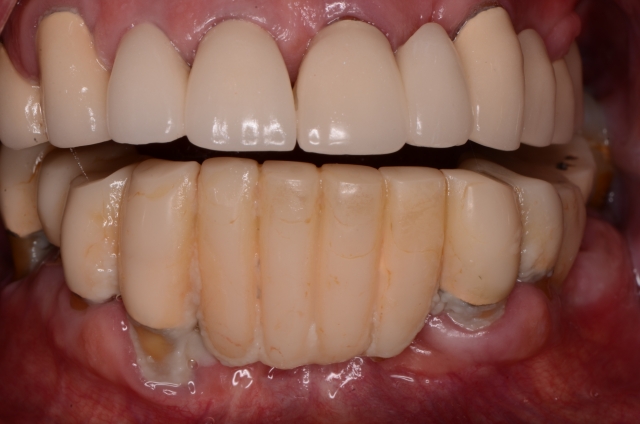

Photography is the linchpin of the entire co-discovery process. We take six pictures in every new case. Spear teaches that these are the six images that will improve case acceptance. Here’s an example:

Rampant root caries, extreme worn dentition and the corrosive effects of GERD are all effectively demonstrated with these photos. These photos get the ball rolling on patients requiring more comprehensive treatments due to a terminal dentition.